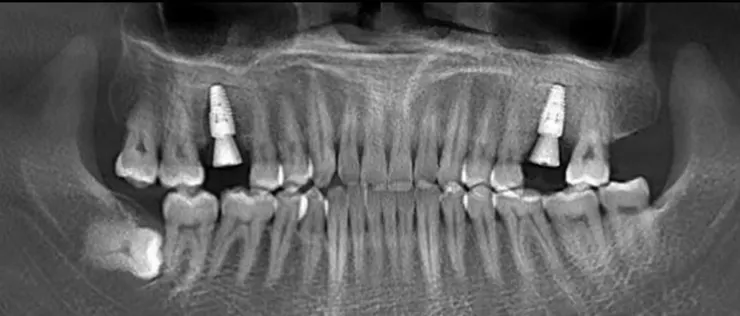

過咗關口直行幾百米就到診所,位置好好揾。姑娘都好熱情,會問我食咗早餐冇,肚餓嘅話有免費嘅麵包仔頂肚。拍完牙片之後,陳醫生仔細睇咗我嘅牙片,制定好方案之後就開始手術啦。

陳醫生手勢好好,除咗打麻葯戈陣有d痛,之後真係冇感覺到痛,兩隻爛牙根剝咗十幾分鐘左右。剝完後麻葯失效,會感覺到牙齒戈度有d痛,但係痛嘅程度可以接受。剝完牙後兩個月複雜,要等骨頭窩生好之後先可以種牙。複診嘅時候,唸起我嘅智慧齒有d痛,陳醫生幫我睇咗下,話裡隻智慧齒最好剝咗佢,唔係嘅話會影響其他牙齒。我唸著等种完牙後再來剝。

種牙比剝牙好,冇痛感,而且好快,種兩隻牙10分鍾搞掂,可能因爲陳主任手勢比較好啦。之後就係取牙模定制牙冠,好快就有新牙喇!